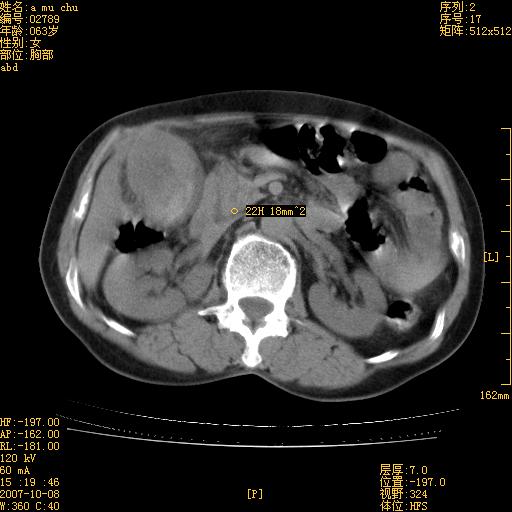

以下是引用卜一在2007-10-17 19:12:00的发言:[br]无增强,很难说!高度可疑:胰头癌?胆囊病变?肝左叶占位?

以下是引用王维浦在2007-10-17 21:02:00的发言:[br]胆囊增大,囊壁明显不规则增厚,邻近肝组织浸润,肝内外胆管无扩张。诊断:胆囊ca;[br]胰头软组织肿块影,考虑是由转移肿大的胰后淋巴结、没有肠道准备的十二指肠及胰头共同形成。[br]

以下是引用zhangzexing在2007-10-18 7:13:00的发言:[br]支持胰头占位,慢性胆囊炎. 2.肝左叶前外侧段占位,血管瘤?建议增强

以下是引用影像实习生在2007-10-17 19:49:00的发言:[br]支持胰头占位,慢性胆囊炎. 2.肝左叶前外侧段占位,血管瘤?建议增强.

以下是引用刘振江在2007-10-17 19:42:00的发言:[br]没有增强,胰头癌?胆囊及肝左叶占位?